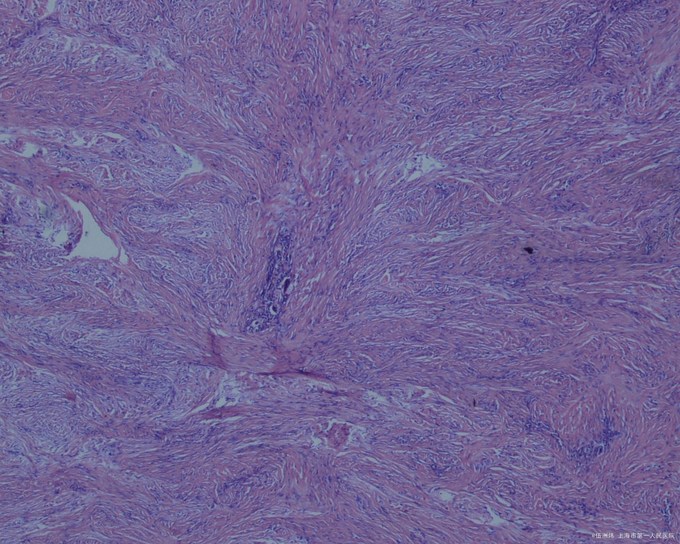

皮损组织病理检查显示结节位于真皮内,无包膜,境界不清,与周围正常组织有明显的交错,下界清楚,上界与表皮之间常夹着一条“境界带”,但瘤组织有时也可与表皮相连。病变组织由成束的成纤维细胞、组织细胞和成熟或幼稚的胶原纤维组织组成,相互交织;病变上方的表皮明显增生,棘层肥厚,皮突延长。偶见有核丝分裂象。

病因 本病的真正病因不明。本病的发生可能是反应性的,与皮肤局部轻微损伤有关,如昆虫叮咬或钝器损伤。亦有人认为与病毒感染也有一定关系。但克隆性分析提示本病是肿瘤性的。 临床表现 多见于四肢伸侧,亦可见于其他部位。皮损表现为圆形或卵圆形丘疹或结节,直径约1cm通常不超过2cm,偶2cm或更大。隆起,坚硬,基底可推动,但与表皮相连。表面的皮肤光滑或粗糙,色泽深浅不一,可为正常肤色,亦可为黄褐色、黑褐色或淡红色。多见于中青年,罕见于儿童,好发于女性。皮损常持久存在,少数可数年后自行消退。通常无自觉症状,偶或有轻度疼痛感。一般为单发,偶或多发。 检查 皮损组织病理检查显示结节位于真皮内,无包膜,境界不清,与周围正常组织有明显的交错,下界清楚,上界与表皮之间常夹着一条“境界带”,但瘤组织有时也可与表皮相连。病变组织由成束的成纤维细胞、组织细胞和成熟或幼稚的胶原纤维组织组成,相互交织;病变上方的表皮明显增生,棘层肥厚,皮突延长。偶见有核丝分裂象。根据肿瘤细胞成分与胶原纤维所占比例分为2种组织类型,即纤维型和细胞型。 诊断 根据临床表现和组织病理检查可以诊断。 1.局部有轻微外伤史。 2.临床表现为皮内丘疹或结节黄褐色或淡红色等,与深部组织不粘连。 3.组织病理检查符合皮肤纤维瘤病理改变。 治疗 一般不需治疗,少数损害数年内可消退。若单个损害有疼痛引起病人痛苦时可行手术切除。皮质类固醇激素皮内注射有一定的疗效。